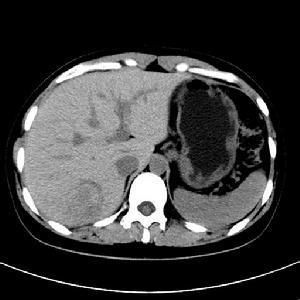

2.CT檢查。CT表現為少血管團塊,有包膜的囊和實質組織,密度低於肝臟。可見肝臟內巨大的密度不均的低密度區可見多個囊性的液性暗區目前CT仍是快速低廉的方法同時可以很好地顯示解剖邊界以便決定手術切除的可能性。